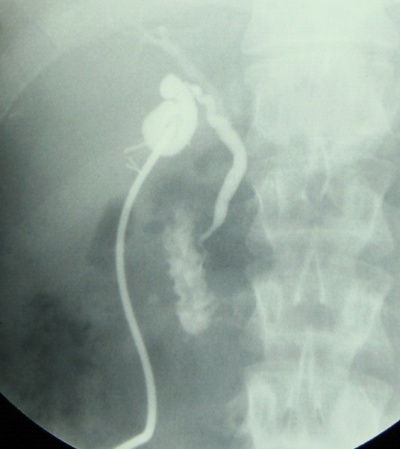

- היצרות הכולדוכוס: ההיצרויות נובעות מפגיעה חבלתית בכולדוכוס, מנזק לכלי הדם שלו, או מקשירה חלקית של הכולדוכוס בזמן קשירת הציסטיקוס (תצלום 24.8).

90%-85% מהחולים המנותחים עקב אבני כיס המרה יירפאו בעקבות הניתוח. השאר ימשיכו לסבול מתסמינים הדומים לאלה שלפני הניתוח ובלא קשר לאבנים נותרות. הסיבה לכך קשורה לרוב באבחנה טרום-ניתוחית מוטעית. אמנם לחולה היו אבנים בכיס המרה, אך לא הן שגרמו לתסמינים, אלא מחלות אחרות שלא אובחנו לפני הניתוח. מחלות תפקודיות, דלקת הלבלב, כיב פפטי, בקע סרעפתי, תסמונת אנגינוטית וכדומה, כל אלה יש בהם כדי לגרום לתלונות של החולה לפני הניתוח ולאחריו. לעתים, התסמינים עלולים להיות קשורים בדרכי המרה, כגון בחולים שבהם הושאר גדם ארוך של צינור כיס המרה, המשתנה שינויים דלקתיים וגורם לכאבים, או היצרות של הפפילה (תצלום 26.8), שלא אובחנה בזמן הניתוח, הגורמת לכאבים או לצהבת חסימתית.